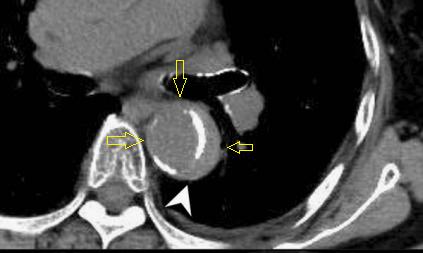

下图的胸部CT平扫,有什么致命的问题?

血管壁钙化啊,老年人很常见啊,

注意,看下面,钙化在血管的里面,不是在管壁!难道是血液钙化了?血液钙化?

这不是血液钙化,这是主动脉夹层导致的血管钙化内移!血液不会钙化,因为动脉夹层,导致钙化的内膜被压迫进入血管!

增强CT一看,就一清二楚了!

不着急!仔细看,血管里面的“血液”居然钙化了!这叫血管钙化内移,要警惕主动脉夹层!有研究发现,血管钙化内移诊断动脉夹层的特异性高达90%。